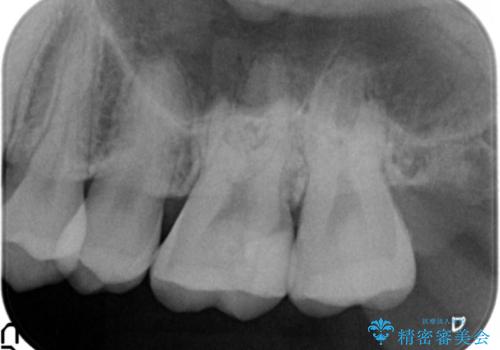

- 奥歯にフロスを通すとにおいがすることを気にされ、来院された患者様です。

精査したところ、奥歯に充填された保険内のコンポジットレジンの適合が悪いことにより、汚れがたまりやすい状態でした。

不適合なレジンを除去し、セラミックインレーによる治療を行いました。(右上76左上67右下7の計5本)